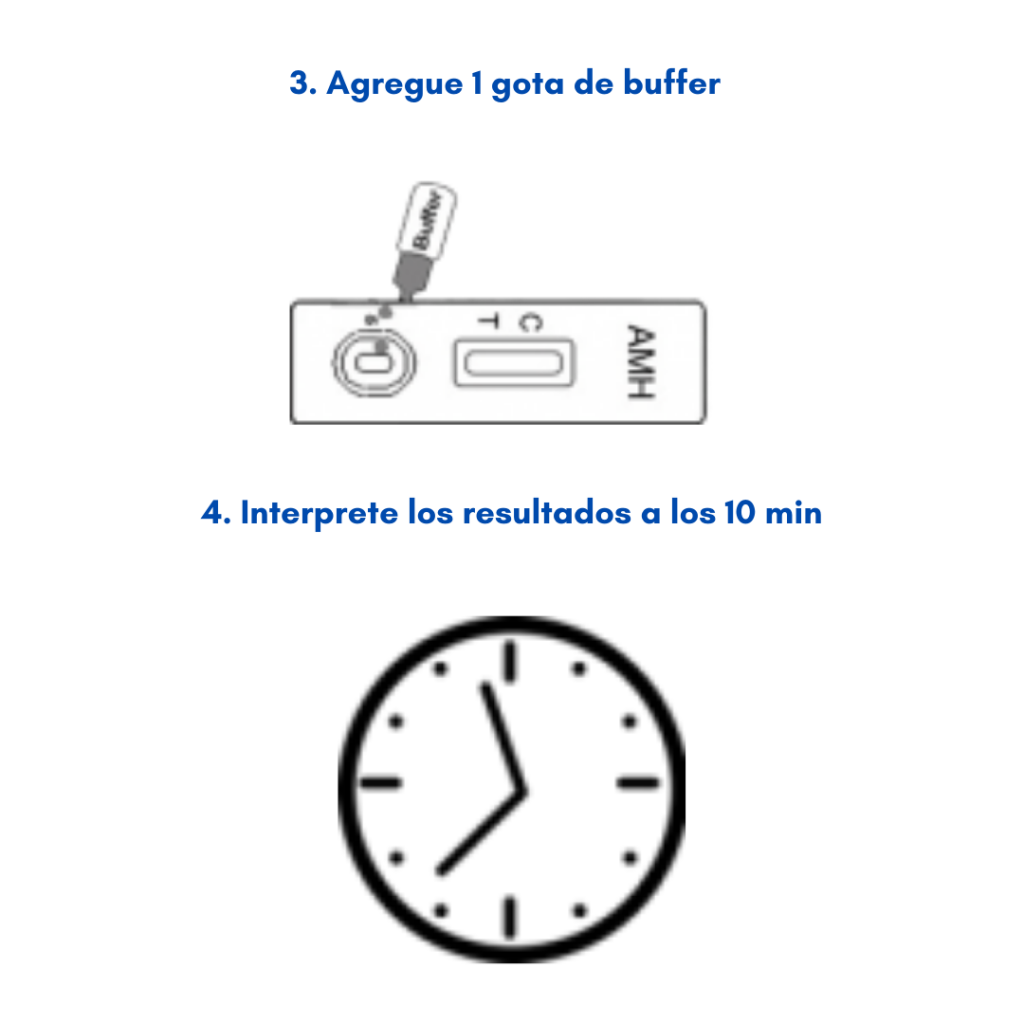

Aquí es donde Hemoglinet redefine el panorama del diagnóstico y control de la diabetes. Esta innovadora prueba de hemoglobina glicosilada (HbA1c) elimina la necesidad de equipos sofisticados y costosos.

Con solo unas gotas de sangre, Hemoglinet permite una detección cuantitativa in situ, lo que significa que el análisis puede realizarse en cualquier lugar, desde un consultorio médico hasta un entorno rural, sin la infraestructura de un laboratorio tradicional.

Si la prueba de Hemoglinet muestra dos líneas encendidas, indica que el nivel de hemoglobina glicosilada del paciente está por encima del 6.5%, un claro signo de descontrol o diagnóstico de diabetes que requiere atención inmediata.